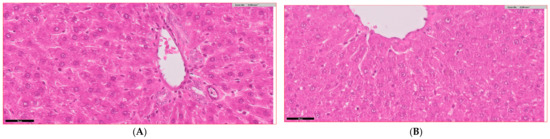

Figure 5 presents the histopathological findings and quantitative assessments of liver tissue from experimental groups. Liver sections from the control group (Figure 5A) display normal hepatic architecture with well-preserved hepatocytes, intact sinusoids, and absence of inflammation or fibrosis, while sections from the Bifidobacterium bifidum-treated group (Figure 5B) are similar to the control. In contrast, the diabetic group (Figure 5C) shows marked hepatocyte degeneration, inflammatory cell infiltration, sinusoidal congestion, and fibrosis. Liver sections from diabetic rats treated with metformin (Figure 5D) exhibit moderate improvements with reduced inflammatory cell infiltration, less hepatocyte degeneration, and lower fibrosis levels. The diabetic group receiving Bifidobacterium bifidum (Figure 5E) shows reduced inflammation, improved hepatocyte morphology, and decreased fibrosis, and liver sections from the group treated with both Bifidobacterium bifidum and metformin (Figure 5F) display the most pronounced restoration of normal hepatic architecture. Quantitatively, the inflammation scores (Figure 5G) increased 4.3-fold in diabetic rats compared to controls (p < 0.001). In the diabetes + metformin group, inflammation was reduced by approximately 35% (p < 0.05), by 49.2% in the diabetes + Bifidobacterium bifidum group (p < 0.05), and by around 65% in the combined therapy group (p < 0.01). Hepatocyte degeneration (Figure 5H) was significantly elevated in diabetic rats (p < 0.001), with reductions of about 45% observed in the metformin-treated group (p < 0.05), 56.8% in the Bifidobacterium bifidum-treated group (p < 0.05), and 70% in the combined treatment group (p < 0.01). The fibrosis index (Figure 5I) increased 3.6-fold in diabetic rats (p < 0.001) and was reduced by roughly 35% with metformin (p < 0.05), 44.3% with Bifidobacterium bifidum (Bifidobacterium bifidum) supplementation (p < 0.05), and approximately 60% with the combined therapy (p < 0.01).

Figure 5.

(A–I) Bifidobacterium bifidum and metformin protect against diabetes-induced liver injury. (A–F) Histopathological liver sections and (G–I) quantitative assessment of liver tissue across experimental groups demonstrate the protective effects of Bifidobacterium bifidum and Metformin—alone and in combination—against diabetes-induced liver injury. (A,B) Liver sections from the control (C) and Bifidobacterium bifidum-treated (B) groups exhibit normal hepatic architecture with preserved hepatocytes and intact sinusoids. (C) The diabetic group (D) shows severe hepatocyte degeneration, inflammatory infiltration, sinusoidal congestion, and fibrosis. (D) Treatment with metformin (D+M) leads to moderate improvement in liver histology. (E) The Bifidobacterium bifidum-treated group (D+B) demonstrates further histological enhancement, with reduced inflammation and improved hepatocyte integrity. (F) The combination treatment (D+B+M) achieves the most pronounced restoration of normal hepatic architecture. (G) The inflammation score increased 4.3-fold in diabetic rats (p < 0.001) but was reduced by approximately 35% with metformin, 49.2% with Bifidobacterium bifidum, and 65% with the combination therapy. (H) Hepatocyte degeneration, significantly elevated in diabetic rats (p < 0.001), was reduced by 45% with Metformin, 56.8% with Bifidobacterium bifidum, and 70% with the combination treatment. (I) Fibrosis levels, also significantly increased in diabetic rats, were reduced by 35%, 44.3%, and 60% following metformin, Bifidobacterium bifidum, and combination therapy, respectively. These findings highlight the hepatoprotective potential of probiotic and pharmacological interventions in mitigating diabetes-induced liver damage. Data are presented as mean ± standard deviation (n = 10), with statistical significance denoted as p < 0.05, p < 0.01, and * p < 0.001 compared to the diabetic group.